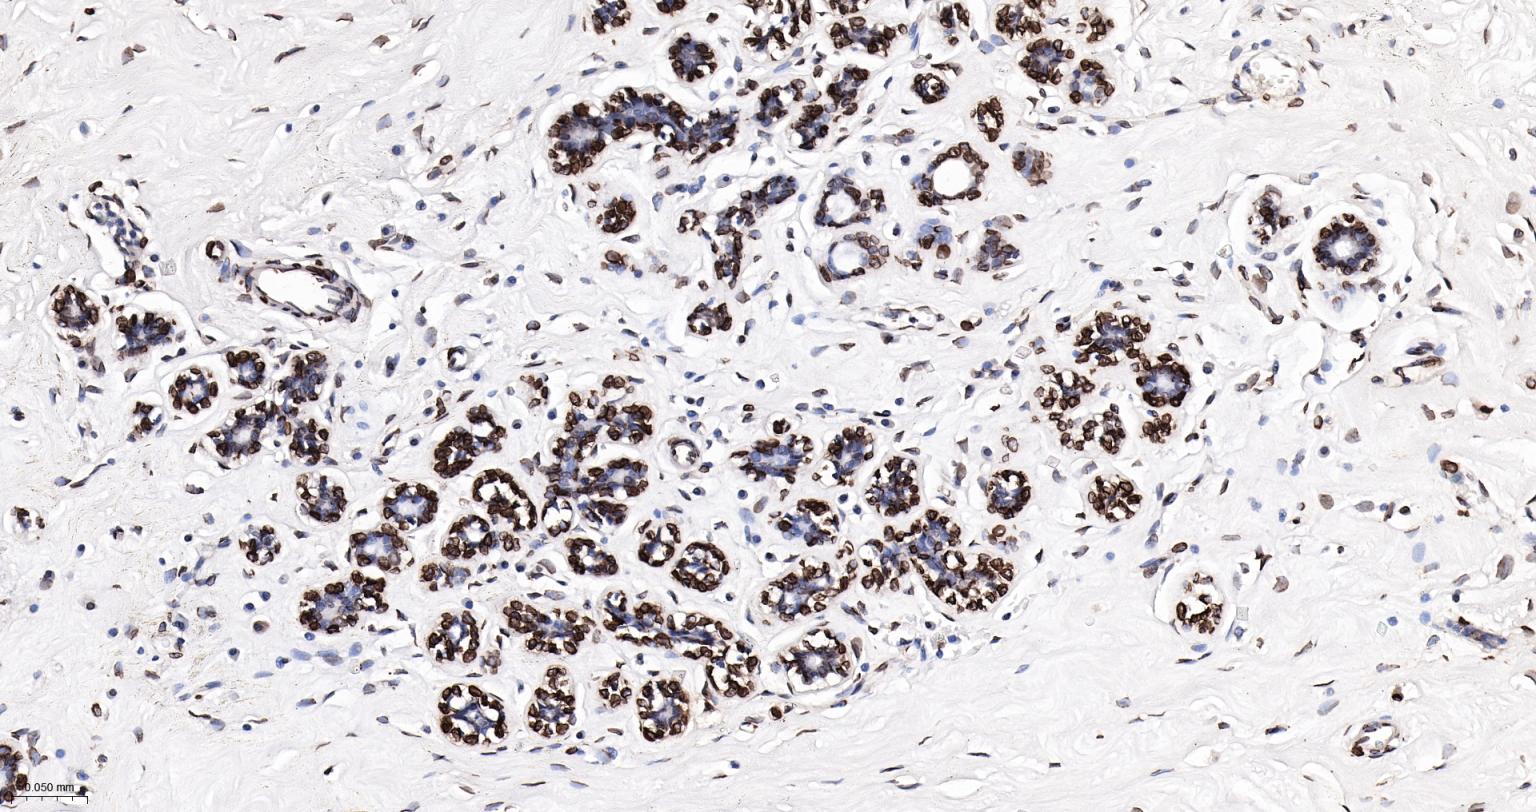

Paraformaldehyde-fixed, paraffin embedded Human Liver; Antigen retrieval by boiling in sodium citrate buffer (pH6.0) for 15 min; The section was incubated with Lamin A/C Monoclonal Antibody, Unconjugated (bsm-62886R) at 1:200 overnight at 4°C, followed by conjugation to the bs-0295G-HRP and DAB (C-0010) staining.